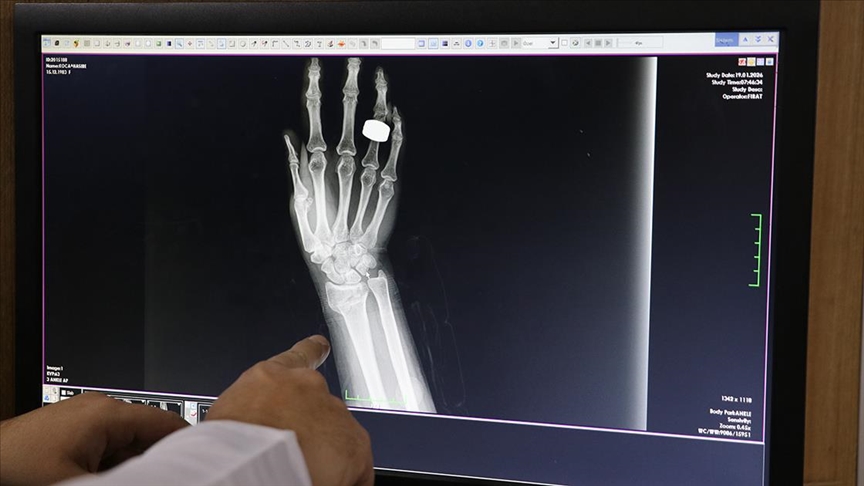

Kar yağışı ve ardından oluşan buzlanmanın düşme vakalarını artırdığını vurgulayan Gül, "Genellikle buzlu zeminde kayma ve araçların kayması sonucu meydana gelen trafik kazaları nedeniyle başvurular oluyor. Bu düşmeler sonucunda el ve ayak bileği kırıkları başta olmak üzere leğen kemiği, kuyruk sokumu ve omurga kırıkları da görülebiliyor." dedi.

"Mermer ve fayans kaplı alanlarda daha dikkatli olunmalı. Düşme sonrası ani şekilde ayağa kalkılmamalı, ağrı, şişlik veya şekil bozukluğu varsa mutlaka sağlık ekiplerine haber verilmeli. Kafa travması özellikle kan sulandırıcı kullanan hastalar için büyük risk taşıyor. Basit görünen baş ağrılarının altında bile ciddi lezyonlar çıkabiliyor. Bu nedenle düşme sonrası mutlaka hastaneye başvurulmalı. Geçen yıla göre düşme vakalarında ciddi artış yaşanıyor. Geçen yıl Elazığ'da yağış azdı. Bu yıl ise son 15-20 günde düşmeye bağlı başvurularımız geçen yıla oranla yaklaşık 2-3 kat arttı. Şu ana kadar düşme nedeniyle hastanemize 600'e yakın bir hasta başvurusu oldu."